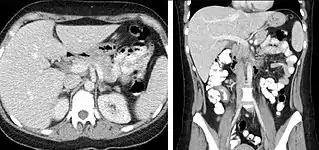

FIGURE 5. Selected images form CT performed using a Cholangiocarcinoma specific protocol. 5a is a portal venous phase image demonstrating a single low attenuation mass which does not appear to enhance. 5b is a 15 minute delayed image which demonstrates delayed enhancement of the liver mass (arrow) characteristic of Cholangiocarcinoma. Several other enhancing masses (arrowheads) are also seen which were not evident on the portal venous phase images.

Delayed phase imaging (figure 5) encompasses scanning at a variety of different times following contrast administration, and depends on the pathology in question. Typical delayed imaging times range from a few minutes to up to 15 minutes or longer. The most common indications for delayed phase imaging are evaluation of the kidneys, collecting system (ureters and bladder) and specific kidney, liver, and adrenal tumors. Evaluation of the kidneys, ureters and bladder are discussed separately in the renal imaging section. Cholangiocarcinoma occurring within the extrahepatic biliary tree or intrahepatic cholangiocarcinomas are a common reason for delayed imaging. Cholangiocarcinomas are fibrotic tumors which enhance slowly, and are usually imaged following a 10-15 minute delay. Similarly, adrenal masses can be evaluated with multiphase imaging including an unenhanced CT, portal venous phase and a 10 minute delay CT which allows for evaluation and calculation of the enhancement and washout characteristics aiding in distinguishing benign adrenal adenomas from other adrenal masses.

Outside of the evaluation of masses, delayed phase images can be used in the evaluation of active vascular extravasation in trauma patients, vascular malformations, and aneurysm disruption.